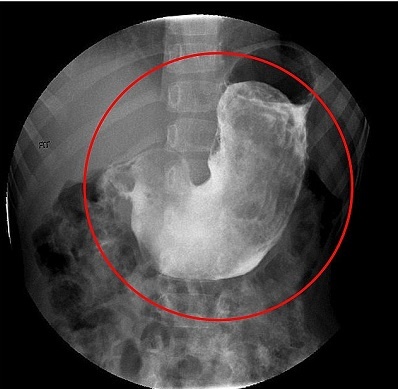

Một bé gái 5 tuổi bị phát hiện có một cuộn tóc lớn gây tắc đường tiêu hóa khiến em không thể ăn uống được. Bé gái được đưa đến khám tại một bệnh viện ở Adelaide, Australia do bị đau bụng ngày càng nhiều đã vài tuần.

Các bác sĩ phát hiện bệnh nhân có tiền sử bị chứng nhổ tóc (trichotillomania) và ăn tóc (trichophagia). Trước đó, gia đình cho biết đã từng thấy tóc trong phân của bé gái và cô bé cũng từng nôn ra cả búi tóc lớn.

Sau khi kiểm tra, các bác sĩ phát hiện một khối lớn, chắc, trơn nhẵn trong bụng đang trướng căng của bệnh nhân. Siêu âm khẳng định bé gái có một lượng tóc lớn trong dạ dày khiến cơ quan này trông giống như một tạng đặc với toàn mô mềm.

Bé gái được chẩn đoán mắc hội chứng Rapunzel, chỉ tình trạng một cuộn tóc lớn (gọi là trichobezar) được tìm thấy trong dạ dày.

Hội chứng này rất hiếm gặp, với chưa đến 120 trường hợp được báo cáo trong y văn và hầu như chỉ gặp ở nữ giới trẻ.